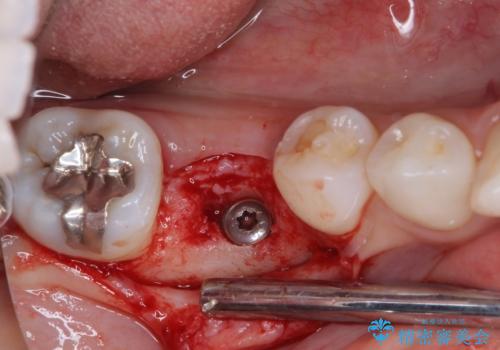

診察の結果、歯が破折しており抜歯が必要でした。

抜歯後にはストローマンSLActiveを埋入し、補綴治療を行うこととしました。